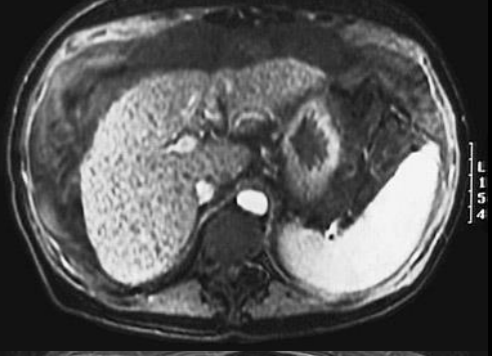

5

Q

A

Estatosis hepatica